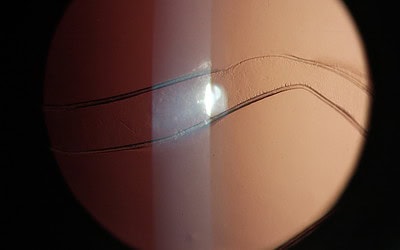

Stries de Haab

Chez des enfants atteints de glaucome congénital, les vergetures de la membrane de Descemet ou stries de Haab apparaissent comme des zones linéaires de déchirure de l’endothélium cornéen mis sous tension, horizontales au centre mais courbes et concentriques à la...